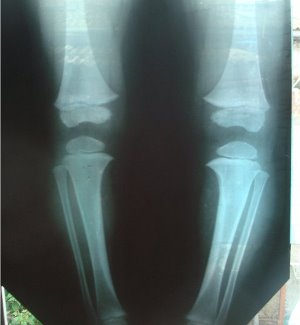

Чтобы определить это заболевание собирается общая клиническая картина. Точно наличие патологии подтверждает рентген. Если есть осложнения, проводят МРТ или КТ.

Болезнь Блаунта (синонимы: tibia vara, синдром Блаунта, синдром Блаунта-Эрлахера-Биезиня-Барбера, болезнь Эрлахера-Блаунта, синдром Мау-Нильсона) — варусная деформация (иногда вальгусная) проксимального отдела большеберцовой кости и внутренняя торсия голени, возникающая вследствие нарушения функционирования медиальной